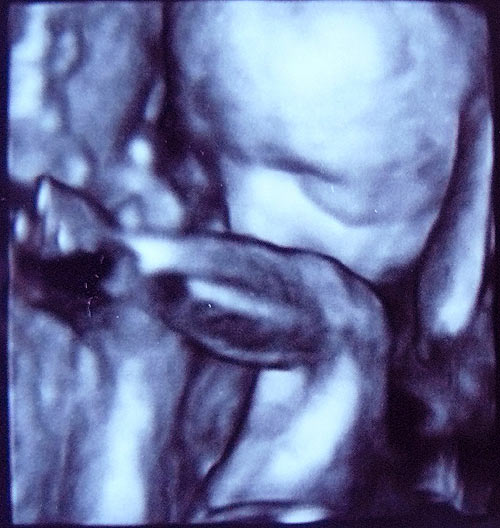

The last major investigation ...

last, but really they are finally behind us. Last week

organ screening with 3-D - ultrasound. The mouse is all right! If I did not make me just before always so crazy. She is now 30 cm and 590 grams. Although I think that since the investigation last week, she has once again risen properly. My waist size has in any case ;-)

And this 3D ultrasound is so fascinating. So I thought she looks all right for girls :-) Even slight resemblance to Lilly * laugh. And as with any ultrasound she plays with hands and feet. Thanks also to you for the words of encouragement. The placenta is actually slipped further up and is no longer in front of the cervix. Three thick XXX ...